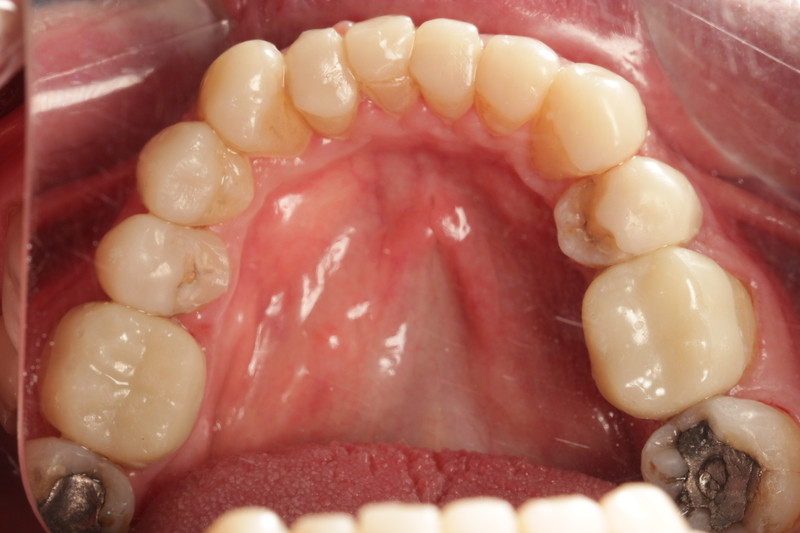

Initial presentation

A male 56-year-old presented with generalised tooth wear and has been a long-standing patient of the practice. He reported no pain or concerns until the extensive wear was highlighted in his examination.

He revealed that he has suffered nocturnal bruxism for many years and has noticed that his teeth have noticeably gotten shorter over the years believing that it was due to natural ‘wear and tear’.

Taking a patient-centred approach, we discussed and highlighted his teeth were at high risk of complete loss of clinical height and pulp involvement. If left unprotected and subsequently required extraction, there would be little room for implants or dentures owing to the alveolar compensation. Thus restoring the dentition in the patient’s later years would prove extremely challenging.

Other challenges

- Alveolar compensation, maintaining occlusal vertical dimension (OVD)

- Shortened clinical crowns with pulp exposure imminent on lower anteriors

- Asymmetrical gingival zeniths

- Buccally positioned canines.